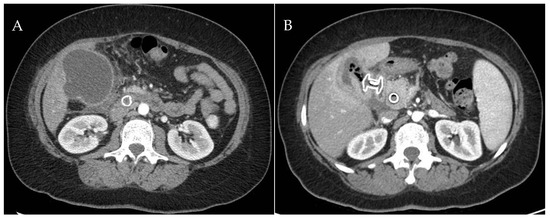

3. EUS-Guided Gallbladder Drainage: Technical Aspects

- Dollhopf, M.; Larghi, A.; Will, U.; Rimbas, M.; Anderloni, A.; Sanchez-Yague, A.; Teoh, A.Y.B.; Kunda, R. EUS-guided gallbladder drainage in patients with acute cholecystitis and high surgical risk using an electrocautery-enhanced lumen-apposing metal stent device. Gastrointest. Endosc. 2017, 86, 636–643. [Google Scholar] [CrossRef] [PubMed]

- Brandaleone, L.; Franchellucci, G.; Facciorusso, A.; Samanta, J.; Moon, J.H.; Vargas-Madrigal, J.; Robles Medranda, C.; Barbera, C.; Di Matteo, F.; Bulajic, M.; et al. The Use of a New Dedicated Electrocautery Lumen-Apposing Metal Stent for Gallbladder Drainage in Patients with Acute Cholecystitis. Diagnostics 2023, 13, 3341. [Google Scholar] [CrossRef] [PubMed]

- Teoh, A.Y.B.; Kongkam, P.; Bapaye, A.; Ratanachu, T.; Reknimitr, R.; Lakthakia, S.; Chan, S.M.; Gadhikar, H.P.; Korrapati, S.K.; Lee, Y.N.; et al. Use of a novel lumen apposing metallic stent for drainage of the bile duct and gallbladder: Long term outcomes of a prospective international trial. Dig. Endosc. 2021, 33, 1139–1145. [Google Scholar] [CrossRef] [PubMed]